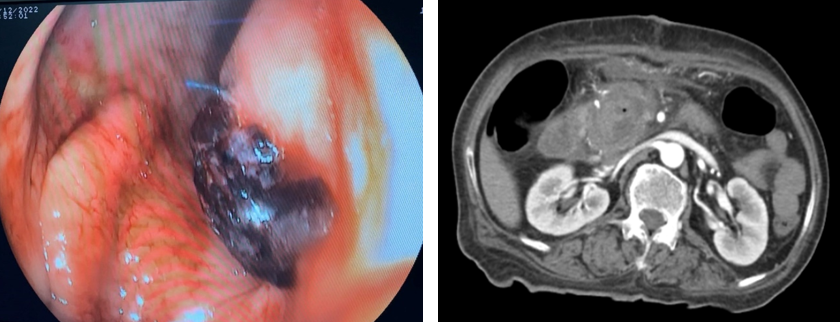

Ghi nhận tại khoa hồi sức tích cực: Bệnh nhân được hồi sức tích cực (có dùng vận mạch), tuyền tổng cộng 5 đơn vị hồng cầu khối, 3 đơn vị plassma, chụp CT bụng có thuốc cản quang, nội soi dạ dày cấp cứu ghi nhận dạ dày sạch, miệng nối không thấy chảy máu, trong nang có nhiều máu đông.

Hình 3 và 4. Hình ảnh chảy máu trong nang (nội soi) và CT scan ngày 15/12